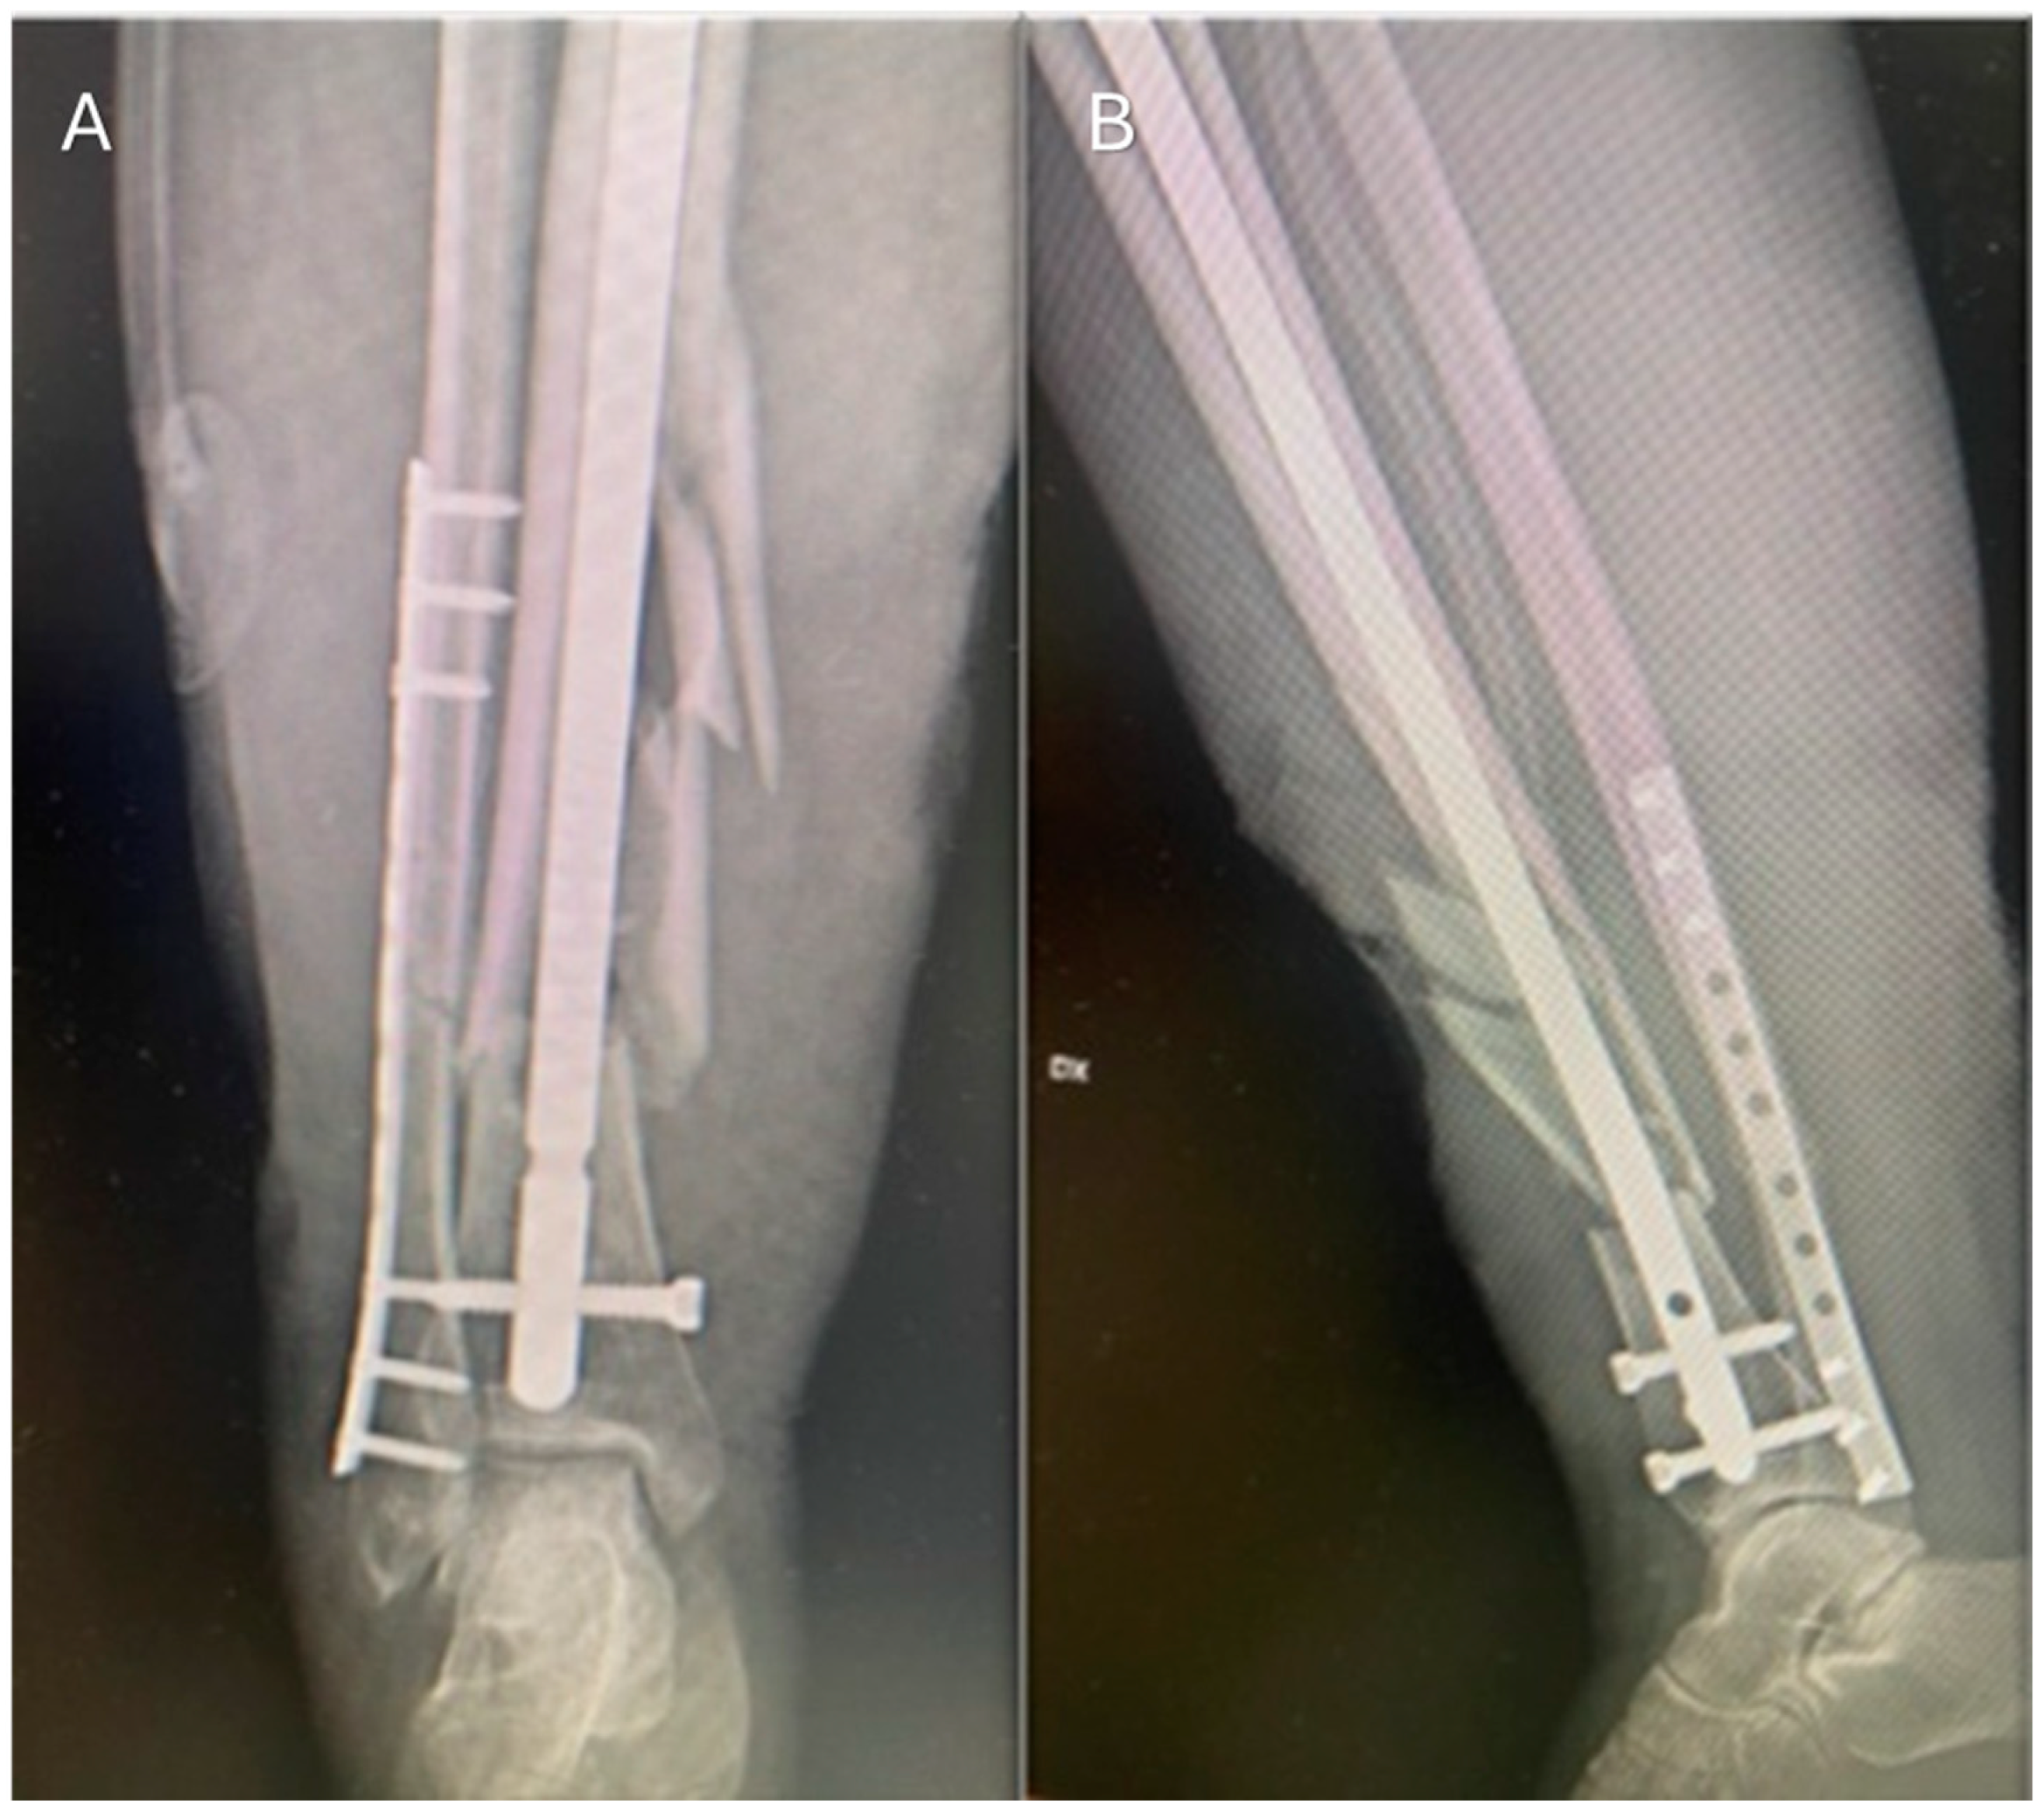

2. Case Presentation